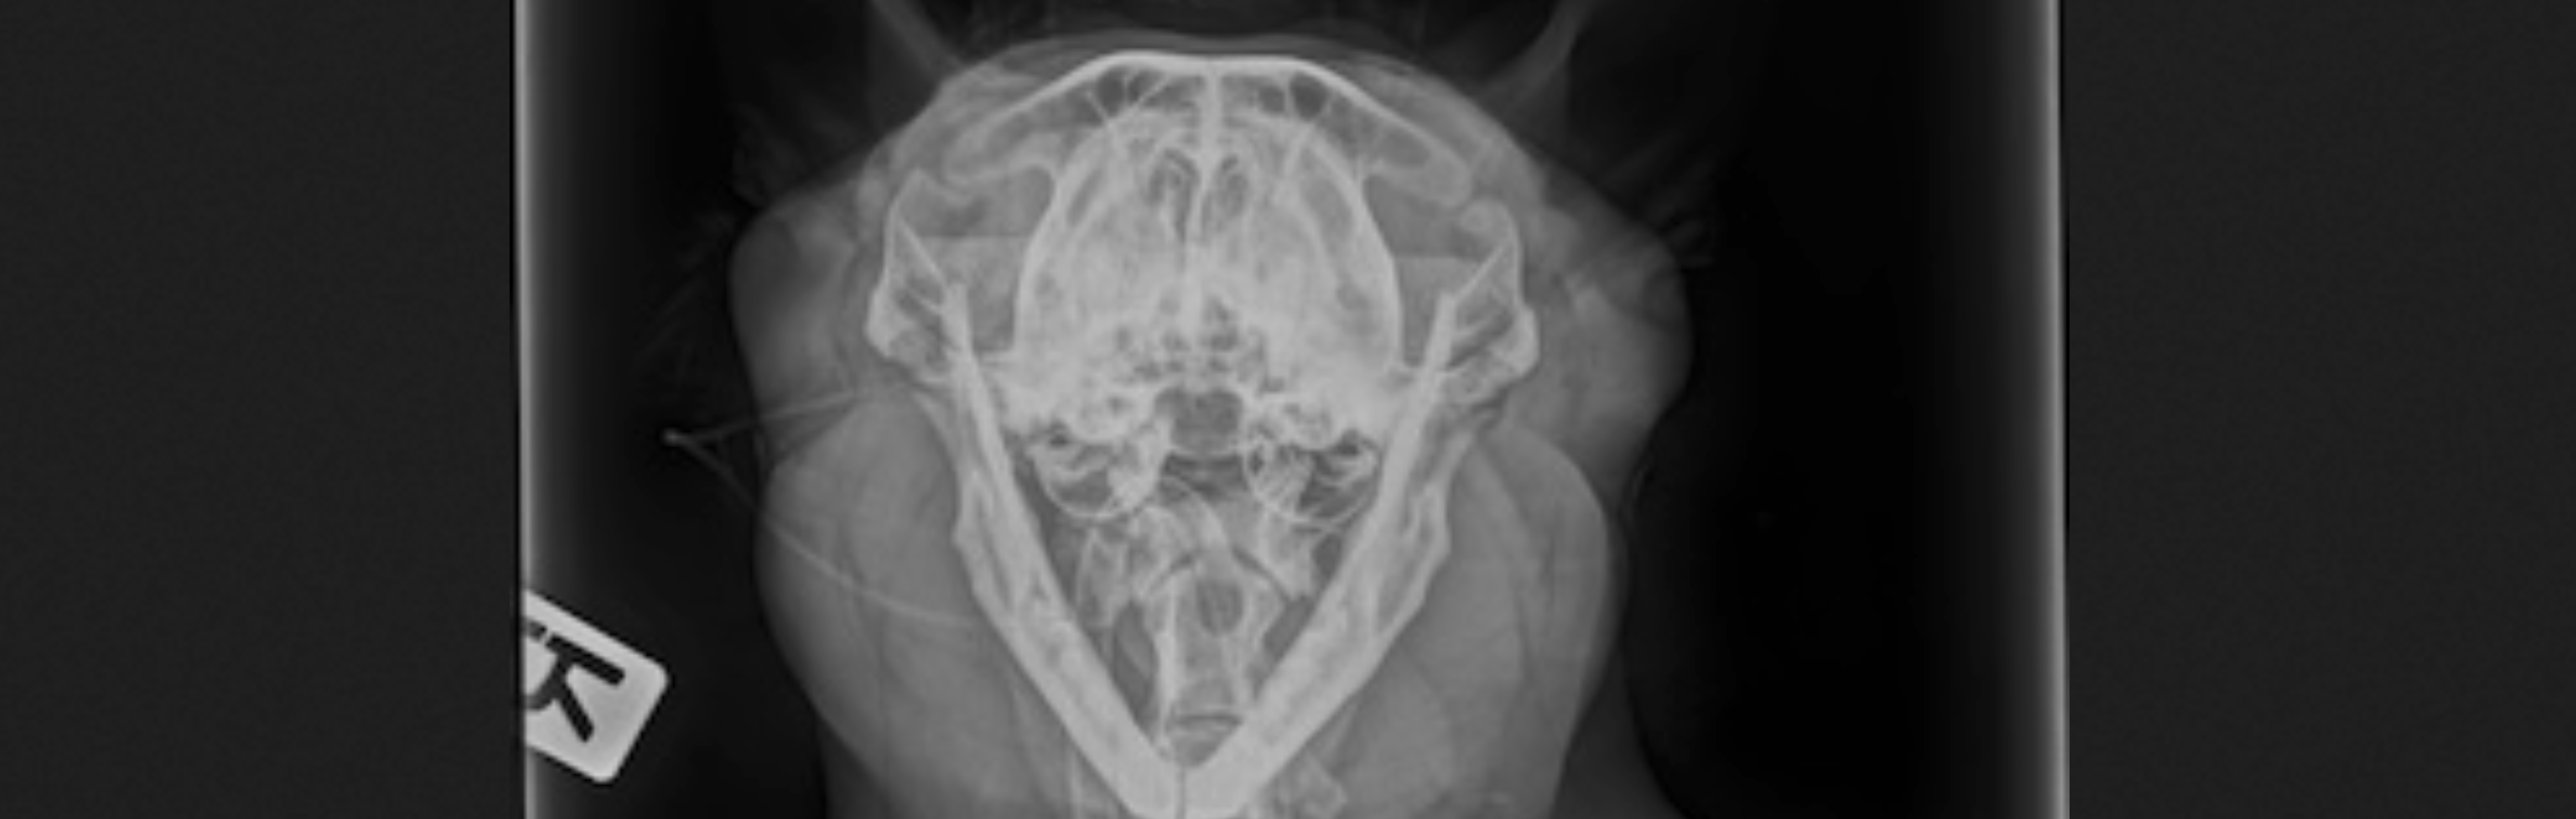

• Digitales Röntgen

• Brachycephales Atemnotsyndrom (häufig bei Bulldoggen und Möpsen):

• Bullaosteotomie